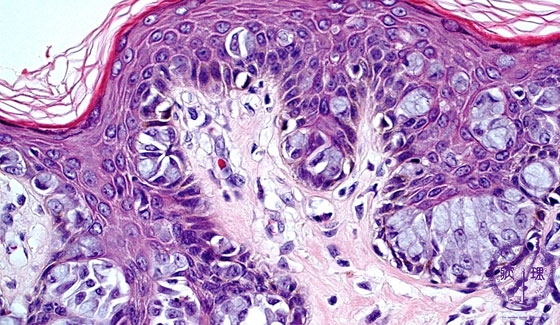

- 14.Breast

- (9)Paget’s disease

Microscopic image(HE stain, high power view):Paget cells can be detected in the full thickness of the skin, but with a strong tendancy to stay within the epidermis. The large nuclei of Paget cells with prominent nucleoli, often pushed aside by intracellular mucous.